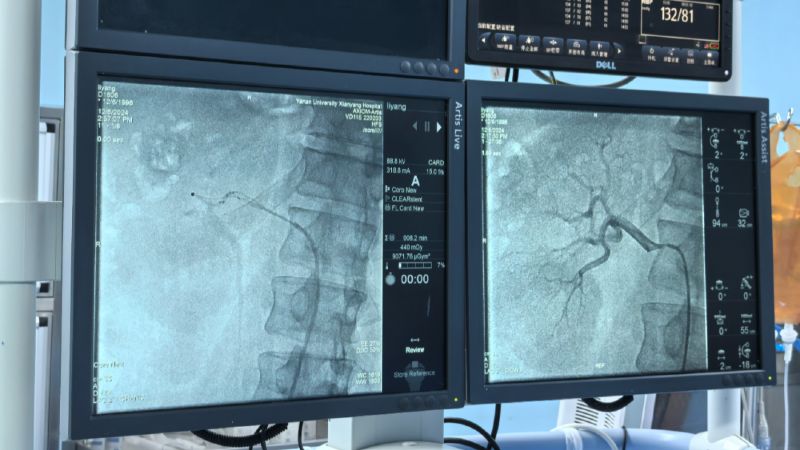

術(shù)中通過對左右腎動脈造影,了解腎動脈解剖結(jié)構(gòu)、評估腎臟灌注情況。而后順利將射頻消融導(dǎo)管的電極頭推至腎動脈主干及分支中遠段,雙側(cè)腎動脈累計消融16次,涵蓋相應(yīng)分支及主干,共完成78個有效消融點,完成后再次行雙腎動脈造影,評價手術(shù)對腎動脈形態(tài)和腎血流影響,累計用時僅60分鐘高效圓滿完成。術(shù)前血壓由154/110mmHg,手術(shù)完成后血壓130/94mmHg,即刻血壓下降效應(yīng)明顯,直至目前術(shù)后減少三種降壓藥物,監(jiān)測血壓維持在120/70mmHg左右,手術(shù)效果理想,長期血壓下降情況我們將持續(xù)隨訪關(guān)注。